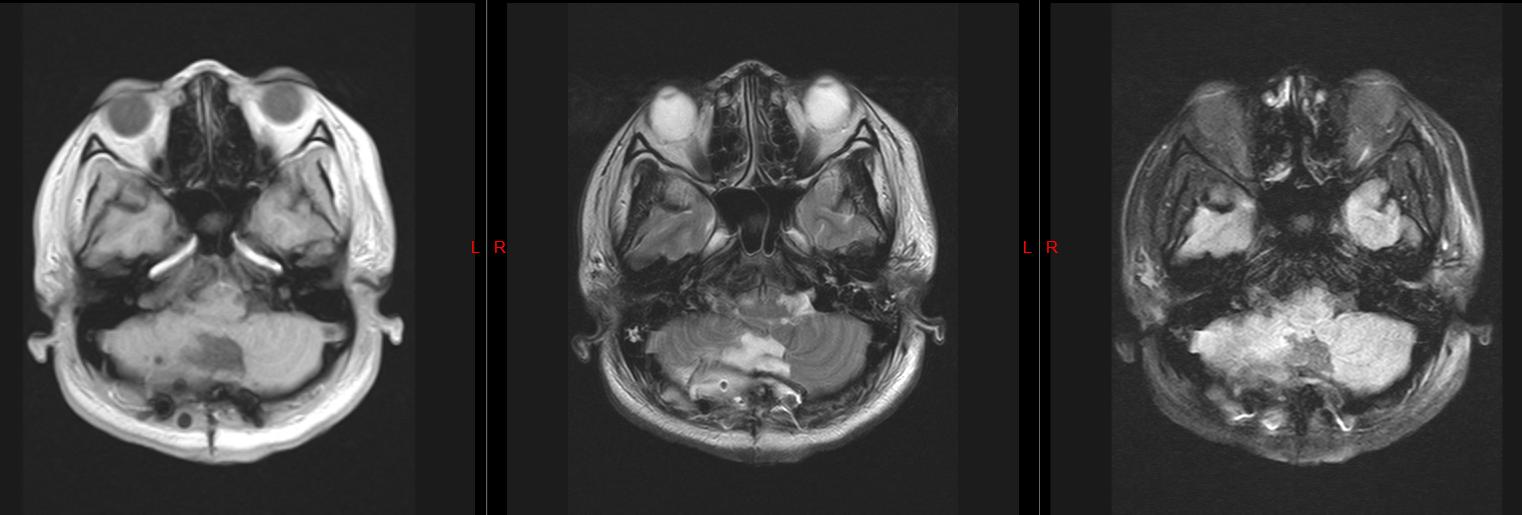

头颅磁共振检查结果显示

我的小脑上长了一个 肿瘤

压迫脑干

并且还有 脑积水

创伤外科二病区主任、主任医师张辉:结合目前症状和影像学检查显示,你的小脑肿瘤考虑皮样囊肿的可能性大,且合并梗阻性脑积水,需要进行手术治疗

皮样囊肿是一种比较少见的颅内先天性良性肿瘤,属 先天性疾病 ,起源于异位的胚胎上皮细胞,是胚胎发育早期在神经沟封闭时将部分皮肤组织带入的结果。

皮样囊肿的基底层内含有较多的纤维组织及真皮层, 内含皮肤的附件如汗腺、皮脂腺及毛囊等

术后复查头颅磁共振

肿瘤完整切除